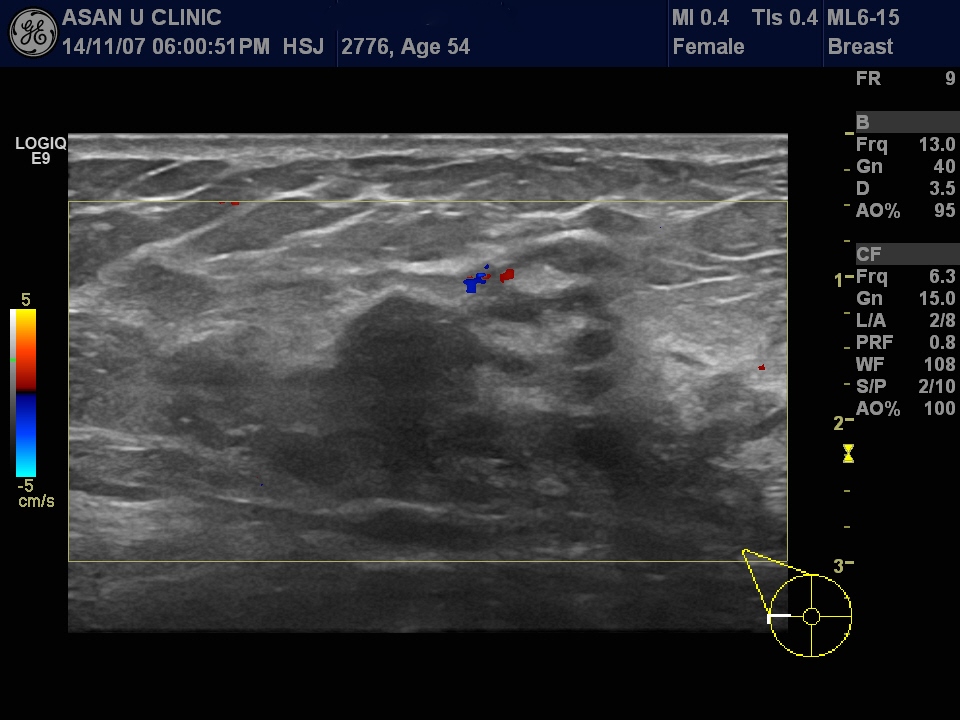

좌측 유방암으로 수술후 5년이상 건강하게 지내시던 분으로

지속적인 우측 가장자리 부분에 통증이 있어 시행한 유방초음파상

이상소견으로 본원에 조직검사 의뢰되셨습니다.

중심핵생검으로 다발성 미세 전이가 의심되긴하나

상피내암으로 진단되었습니다.

최종확정 수술을 해봐야 알겠지만

이번에 진단된 우측 유방암은 상피내암일경우 0기,

미세전이가 확진될 경우 1기가 됩니다.